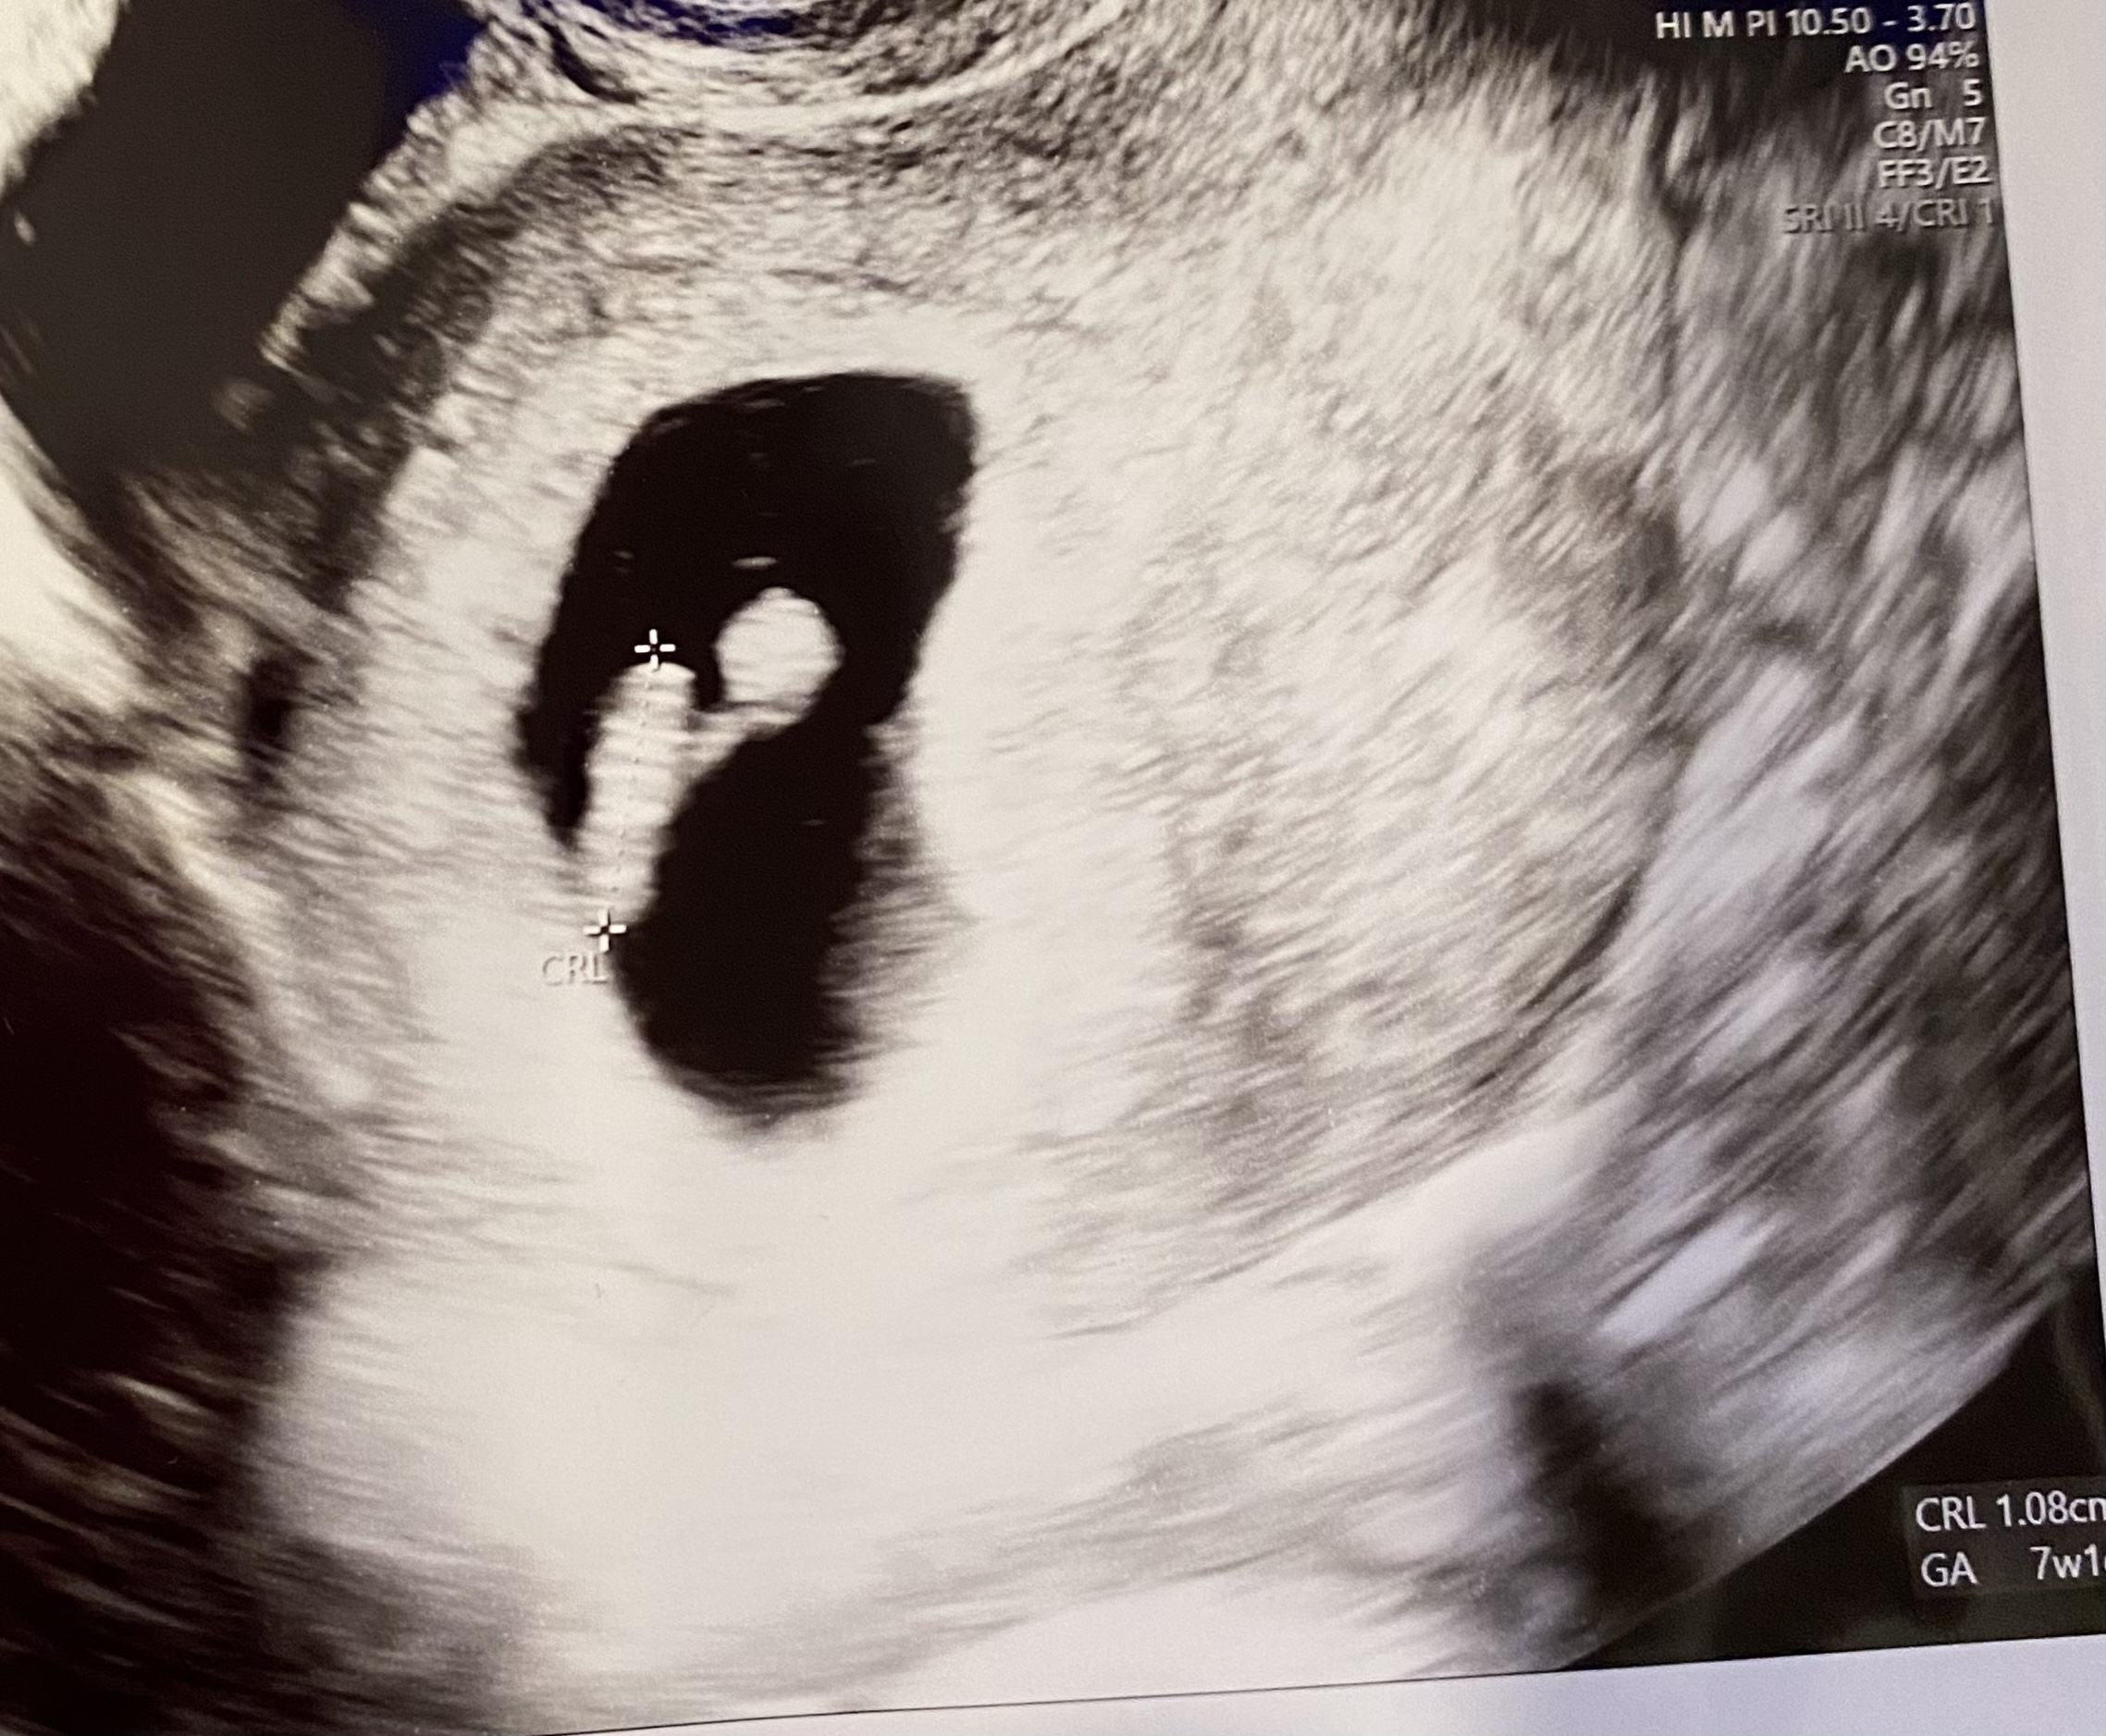

Got our ultrasound on the 21st at 7 weeks! 160 bpm and measuring exactly at 7 weeks! Next appt is in January and getting bloodwork done and to find out the gender 🤩